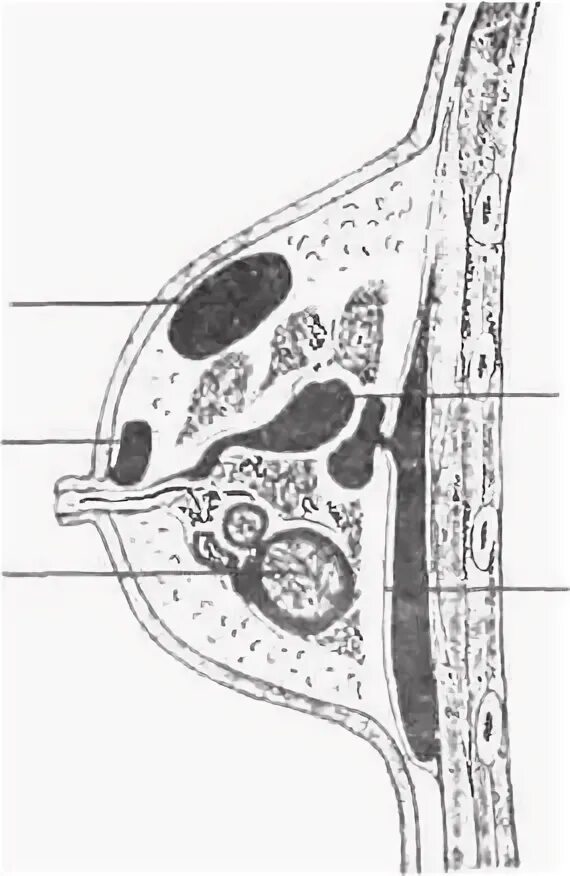

Мастит по студенцову